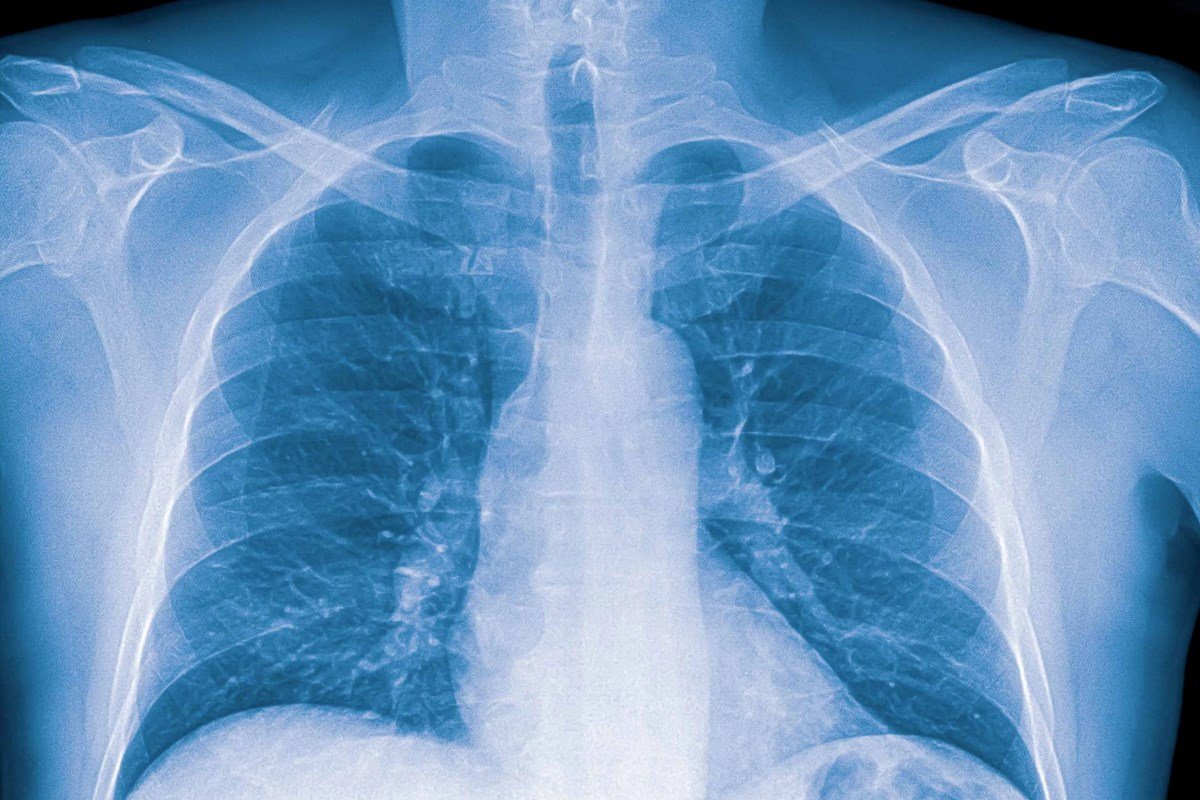

Al respecto, el profesional de la salud recordó que “la neumonía es una infección respiratoria” que consiste en “una infección de pulmón, que generalmente se da en esta época del año y en los meses fríos más que nada”, para la que “los agentes causales pueden ser virus y bacterias que afectan a cada grupo etario”.